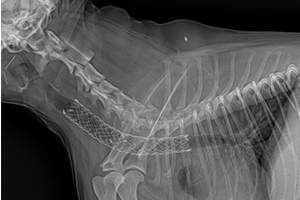

폐동맥 협착증 풍선확장술 시술 중인 모습

폐동맥 협착증(PS) 풍선확장술 시술중인 모습